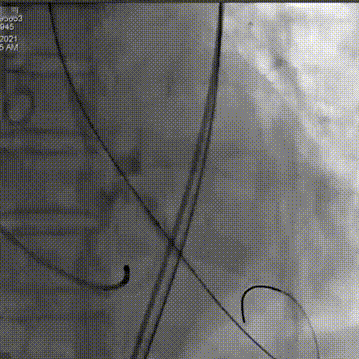

术中影像

主动脉根部造影可见重度钙化

22mm球囊预扩

瓣膜第一次释放

未达到最佳位置,完全回收

重心定位后,第二次释放到瓣膜工作位,发现LCA灌注缝隙狭小

预置LCA保护

完全回收,第三次定位释放,瓣膜位置良好

瓣膜工作位释放“烟囱支架”

瓣膜完全释放后22mm球囊后扩

释放后造影